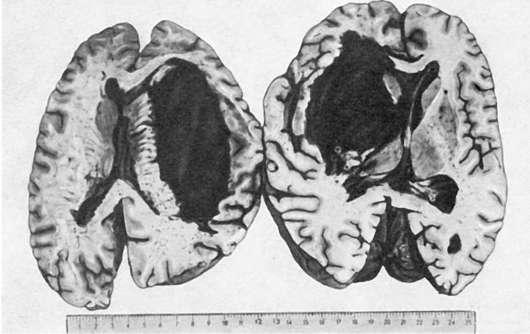

Патологическая анатомия. Морфология транзиторной ишемии головного мозга представлена сосудистыми расстройствами (спазм артериол, плазматическое пропитывание их стенок, периваскулярный отек и единичные мелкие геморрагии) и очаговыми изменениями мозговой ткани (отек, дистрофические изменения групп клеток). Эти изменения обратимы; на месте бывших мелких геморрагий могут определяться периваскулярные отложения гемосидерина. При образовании гематомы мозга, которая встречается в 85% при геморрагическом инсульте, находят выраженную альтерацию стенок артериол и мелких артерий с образованием микроаневризм и разрывом их стенок. В месте кровоизлияния ткань мозга разрушается, образуется полость, заполненная свертками крови и размягченной тканью мозга (красное размягчение мозга). Кровоизлияние локализуется чаще всего в подкорковых узлах головного мозга (зрительный бугор, внутренняя капсула) и мозжечке. Размеры его бывают разными: иногда оно охватывает всю массу подкорковых узлов, кровь прорывается в боковые, III и IV желудочки мозга, просачивается в область его основания (рис. 164). Инсульты с прорывом в желудочки мозга всегда заканчиваются смертью. Если больной переживает инсульт, то по периферии кровоизлияния в ткани мозга появляется много сидерофагов, зернистых шаров, клеток глии и свертки крови рассасываются. На месте гематомы образуется киста с ржавыми стенками и буроватым содержимым. У больных,

Рис.

164. Кровоизлияние в головной мозг с прорывом в боковые желудочки (геморрагический инсульт)